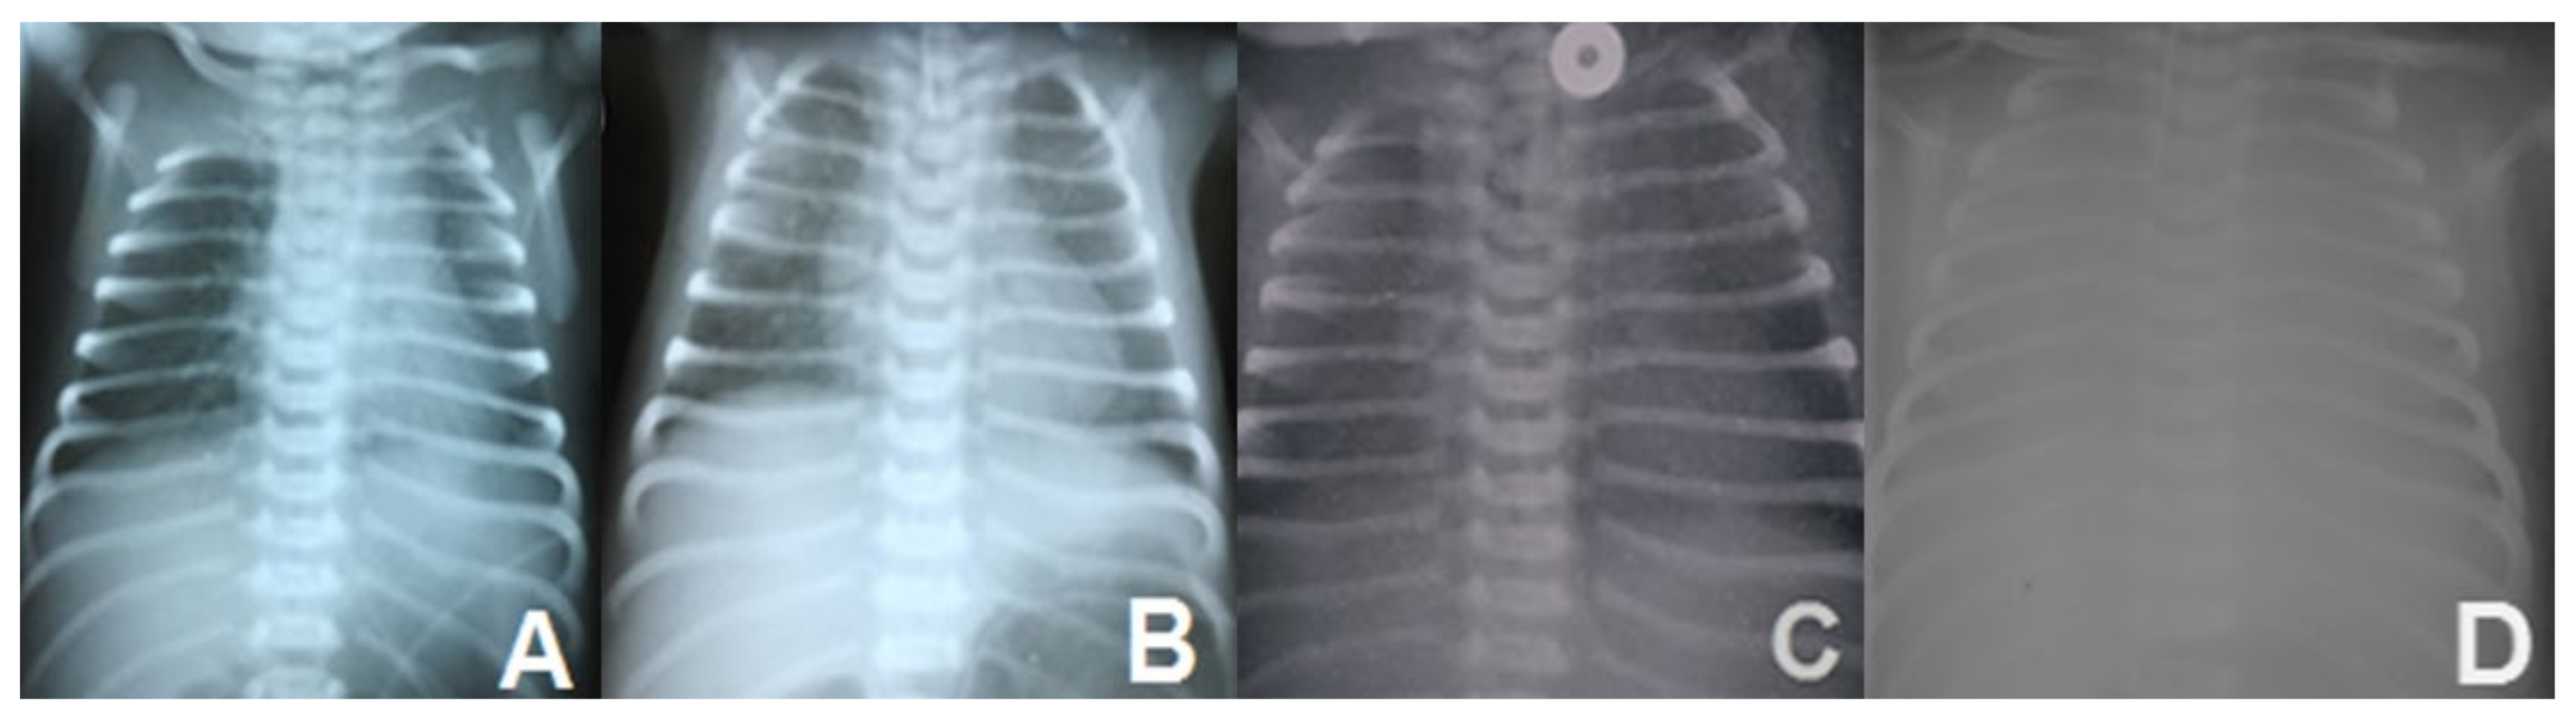

| 10. | Ognean et al., 2024 (this study) | Male | 37 weeks | 2700 g | Severe nRDS – advanced respiratory support (HFOV), prednison, azithromycin, hydroxychloroquine treatment | Thoracic x-ray – ground glass homogeneous opacity | CPI pattern with lobular remodeling, prominent AEC II hyperplasia, focal PAP pattern and extensive DIP-like areas, alveolar proteinosis | N/A | p.Arg280Cys (R280C, c.838C>T, rs201299260)/heterozygous/paternal origin | p.Gln233ter (Q233X, Q233*)heterozygous/maternal origin | SFTPB p.Val267Ile | No, healthy parents, one healthy sibling despite carrying p.Gln233ter and SFTPB p.Val267Ile variants | Died at 77 days of life | Current case report |